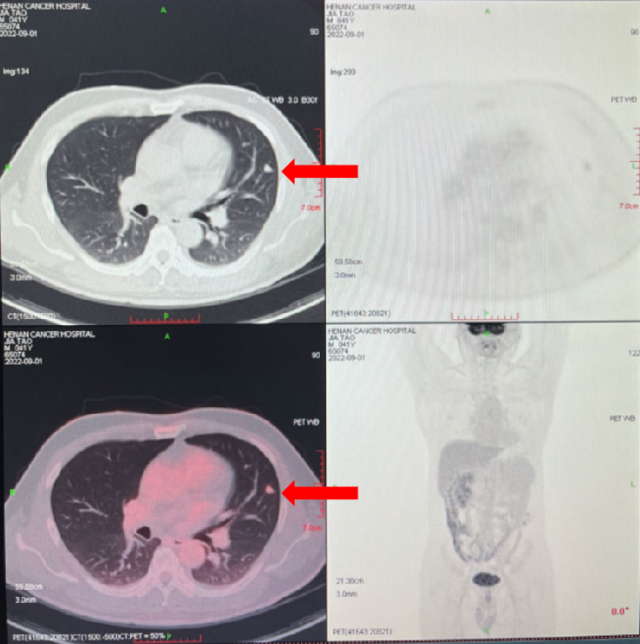

2023-08-01: